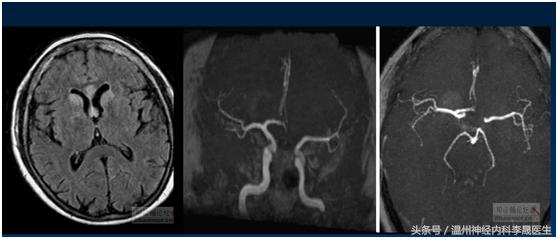

附上一组经典的CT片跟MRI片

先看个病例,女,46岁,主诉;反应迟钝、走路不稳半月。既往史;“高血压”病病史3年,不规律服药,血压控制不详

查体:神经系统:左上肢及右侧肢体肌力5级,左下肢肌力4级,左上肢指鼻试验欠准,与右上肢完成同一动作时笨拙,有时不自主阻挡右手动作,双侧肢体感觉正常,行走似稍宽基底。病理反射未引出。NIHSS评分3分